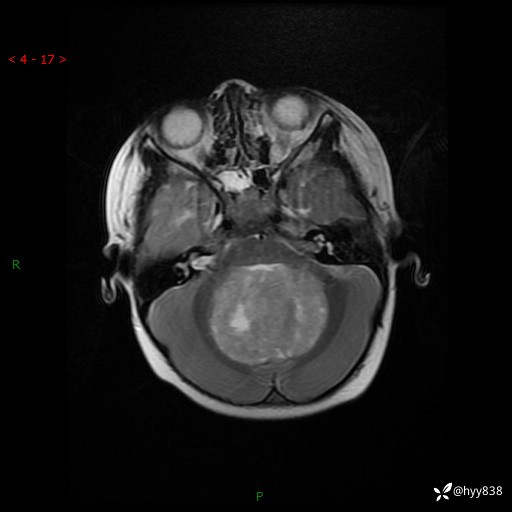

性别:女

年龄:3岁

简要病史:发现行走不稳2个月,加重1个月

颅脑CT平扫

颅脑MRI平扫+增强